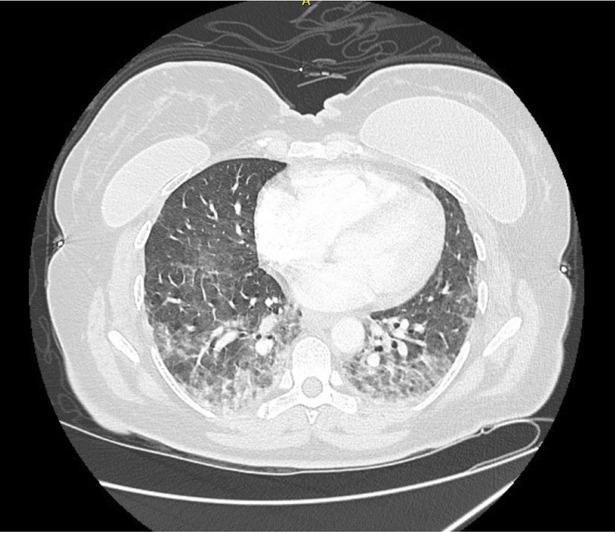

Fig. 2